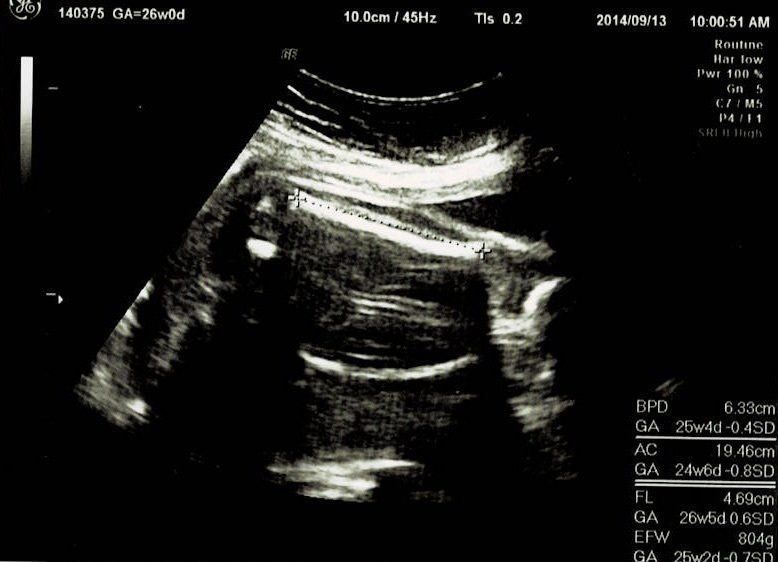

妊娠26週目エコー写真 妊娠中期検査 赤ちゃんのニッコリ顔発見!

妊娠中期検査ということで再び血液検査をしました。今回はHTLV-1(ヒトT細胞白血病ウイルス)とクラミジア抗体のチェックです。さらに血糖検査で、気の抜けたサイダーみたいなブドウ糖液を飲み、60分後の血糖値を測りました。赤ちゃんは前回と同じく、BPD、AC、FLを測ってもらい発育をチェック。赤ちゃんの推定体重は804g。3Dエコーでは、こっちを向いて笑っている(?)表情が見られました。